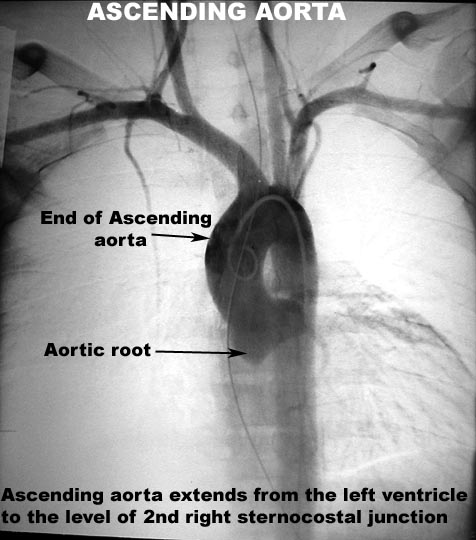

Ascending Aorta

- Arises from the base of LV, runs up

towards right and extends

up to the upper border of second right sternal costal junction.

- 5 cm in length, 2.5-3 cm in diameter